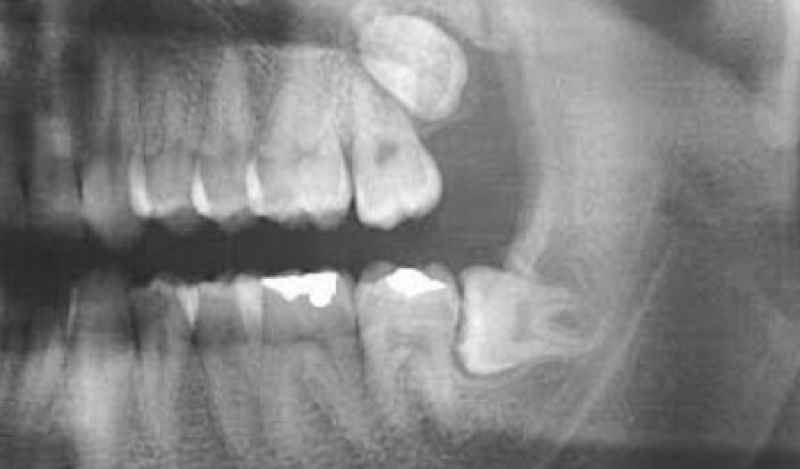

Os dentes do siso, também conhecidos como terceiros molares, geralmente começam a erupcionar na fase final da adolescência ou no início da vida adulta. Em muitos casos, esses dentes não emergem completamente ou crescem de forma impactada, o que pode causar dor, infecção, e danos aos dentes adjacentes. A cirurgia para removê-los é recomendada quando não há espaço suficiente na boca para acomodá-los ou quando eles começam a causar problemas.